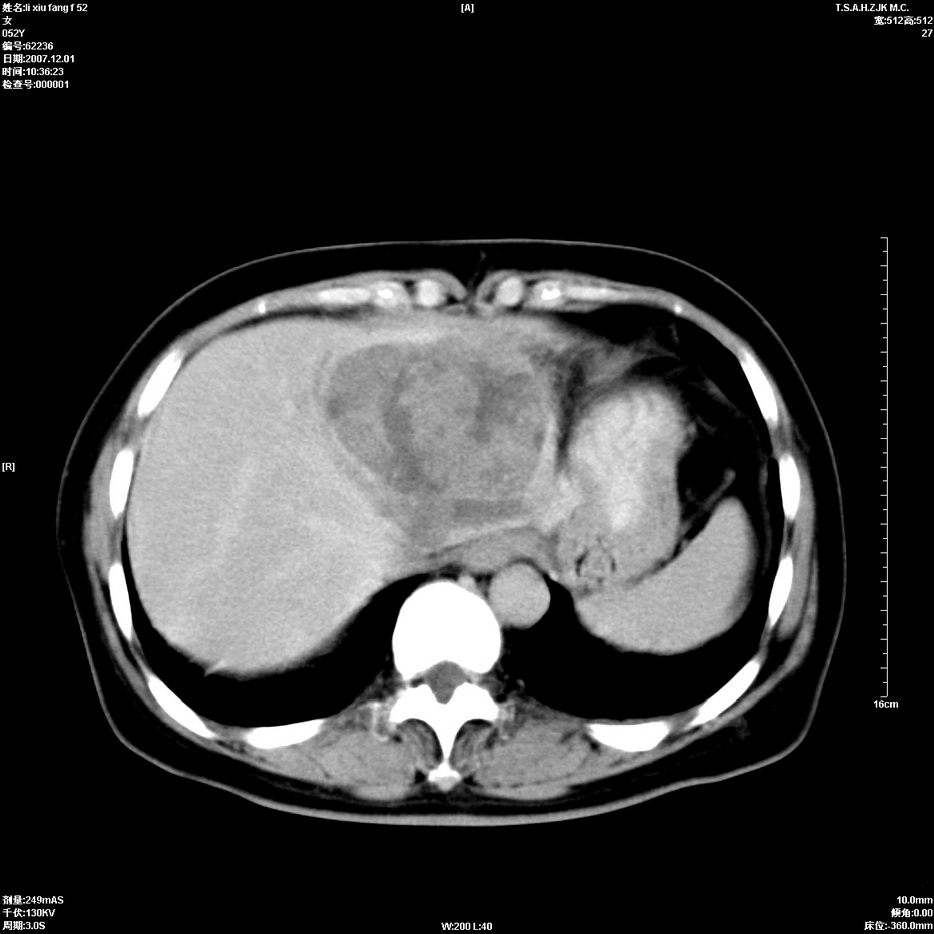

标题: CT12858:女,52岁,胎甲球蛋白861肝左叶占位,肝癌。下腔静 [打印本页]

标题: CT12858:女,52岁,胎甲球蛋白861肝左叶占位,肝癌。下腔静

肝左叶巨大低密度灶肿块,增强符合快进快出表现,有动静脉交通支;静脉期,下腔静脉内有充盈缺损,afp明显升高,支持肝癌并下腔静脉癌栓形成。

以下是引用拾荒者在2008-4-15 22:57:00的发言:[br]肝左叶巨大低密度灶肿块,增强符合快进快出表现,有动静脉交通支;静脉期,下腔静脉内有充盈缺损,afp明显升高,支持肝癌并下腔静脉癌栓形成。